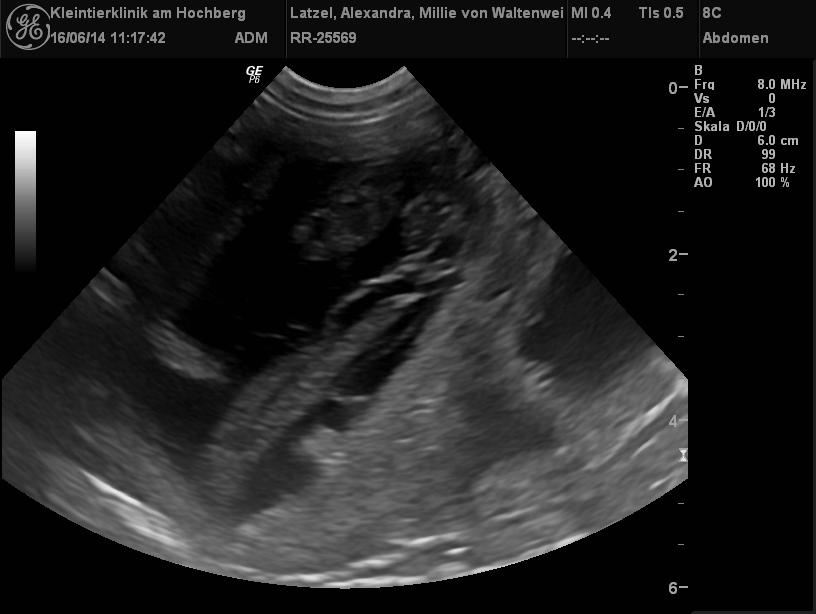

| 25.06.2014 |

| Hurra, Millie ist schwanger! |

| Millie war zum Decken bei Vincent vow for verity von der kleinen Arche!

Sie sind ein wirklich schönes Paar! Nun freuen wir uns sehr auf die Welpis aus dieser Verbindung, die wir Mitte Juli erwarten! |

| Hier die Ultraschallbilder zum Beweis |